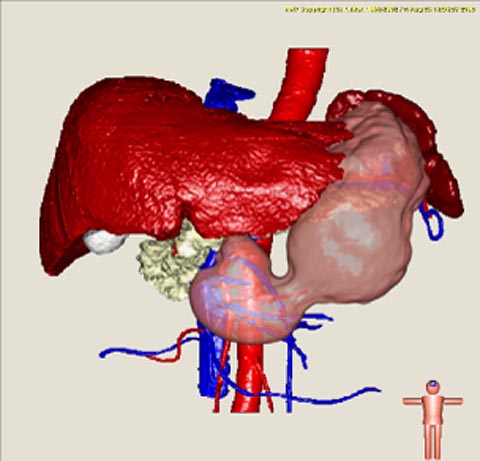

患者さんの解剖学的な構造は一人ひとり異なるため、手術前に撮影されるCT像を用いて、各患者さんの臓器位置、形状、血管分岐パターンなどを解析します。そして、この解析結果を、コンピュータグラフィックスの技術により3次元的に可視化します。CT像から臓器が存在する領域を取り出す処理はセグメンテーション処理と呼ばれています。最近では、大規模な医用画像データベースとそれに付与されたラベル画像から、未知画像に対して精度よく臓器領域を抽出手法が実現されています。さらに、血管などには解剖学的名称が自動的に対応付けられます。このような結果を基にして、個々の患者さんの3次元画像を構築し、手術シミュレーション画像として利用します。また、臓器変形などをシミュレーションすることもできます。

図2 CT像からの腹部臓器セグメンテーションの例